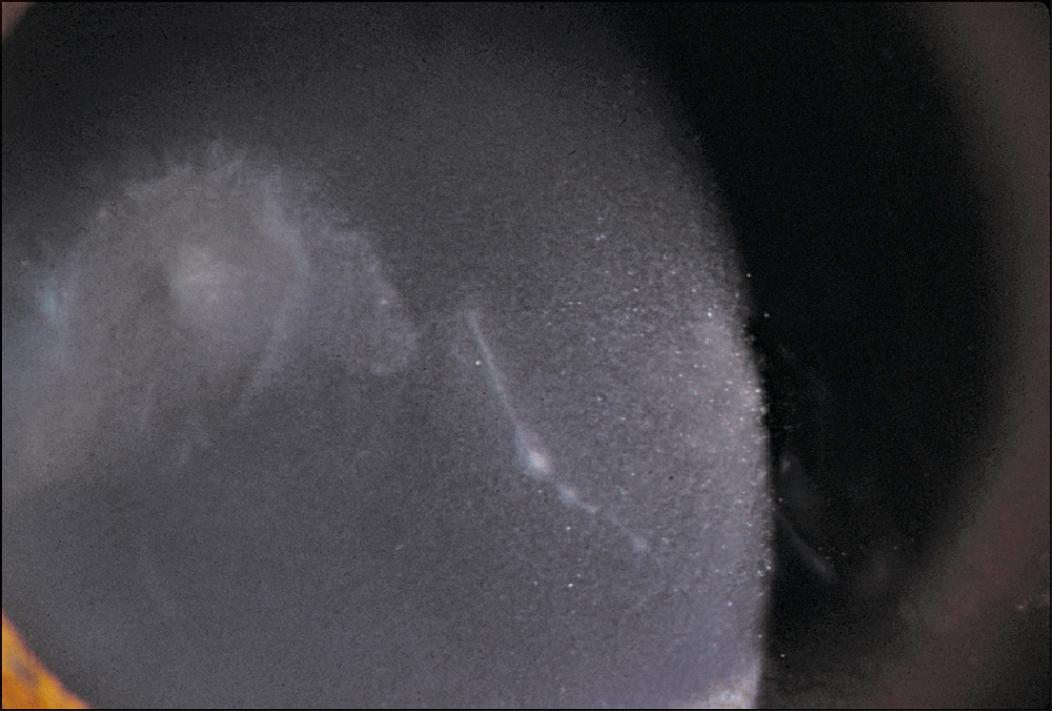

Fig. 99.7, This large paracentral ulcer and radial keratoneuritis presented in a daily-wear lens wearer who correctly cared for her lenses.